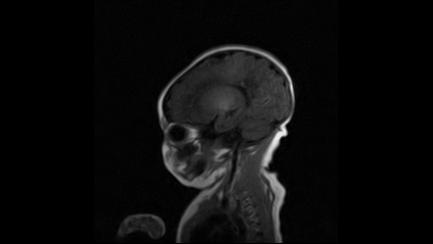

标题: PED3413:患儿女6天体检

缺血缺氧性脑病

6天为新生儿,髓鞘发育正常;左侧颞顶叶蛛网膜下腔增宽,请结合临床。

1。缺血缺氧性脑病2。左侧颞顶叶外部性脑积水,可观察

半卵圆中心上方层上可见对和乐大脑皮质t1高信号,考虑有hie可能,不知有何症状,建议加做dwi及复查

符合缺氧缺血性脑病影像表现。